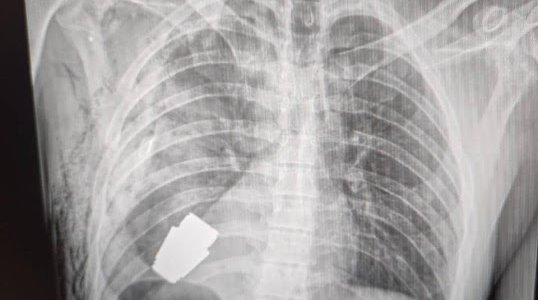

Военный хирург удалил из тела воина гранату, которая не..

Заместитель Министра обороны Украины Анна Маляр рассказала о потрясающей операции, которую совершил военный хирург. В госпиталь поступил украинский защитник, в...